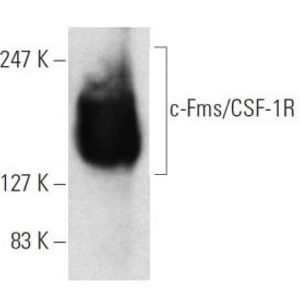

APR 22, 2016Health & MedicineMacrophages exist in every type of body tissue, in the lungs as alveolar macrophages and in the liver as Kupffer cells. ...